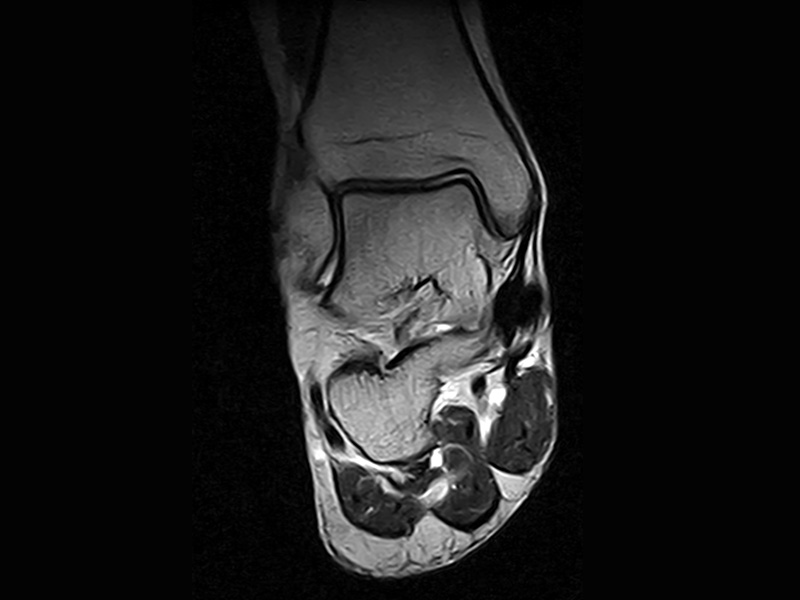

Klinické snímky